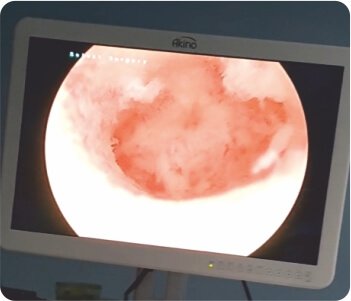

Empty uterus after the procedure